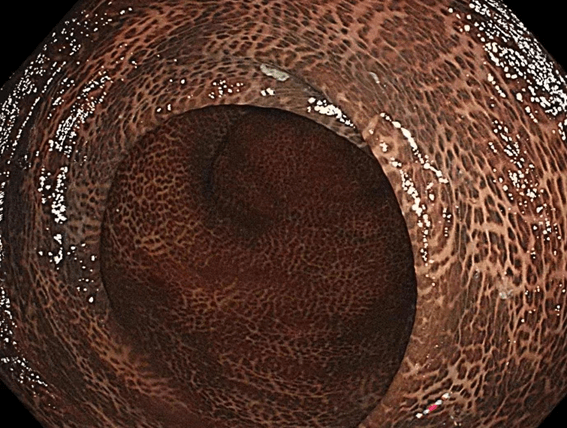

作为每天在镜下与肠道“对话”的内镜人,我们最熟悉健康肠道的温润粉嫩——那是黏膜细腻、血管纹理清晰的生命力,也最揪心于那些布满棕黑花斑的“豹纹肠”,每一道纹路,都是肠道发出的绝望求救。

从业这些年,我们见过太多令人惋惜的场景:患者因长期便秘依赖“排毒茶”、“清肠丸”,直到腹胀难忍才来做肠镜,镜下的肠道早已被蒽醌类泻药染成深浅交错的“豹纹”,就是医学上常说的结肠黑病变!而更可怕的是,部分重度黑变的肠壁下,还隐藏着被掩盖的息肉甚至早期病变。我们总忍不住想:如果他们早一点做肠镜,早一点发现肠道的“变色预警”,早一点停下滥用泻药的行为,何至于让肠道走到这一步?

“豹纹肠”不是突然出现的。长期便秘时,很多人不愿就医,反而迷信“一泻了之”的刺激性泻药,却不知番泻叶、大黄、芦荟、决明子这类成分,会反复灼伤肠黏膜,让上皮细胞凋亡后的脂褐素层层沉积,就像给肠道“刷上墨渍”,最终形成不可逆的“豹纹”。更致命的是,黑变的肠壁会模糊病变信号,让我们在镜下难以分辨息肉与正常黏膜,极易延误最佳治疗时机。而这一切,通过一次肠镜就能提前规避——它不仅能直观看到肠道是否开始“变色”,还能精准发现早期息肉、炎症,甚至在镜下直接切除隐患,是守护肠道的“火眼金睛”。